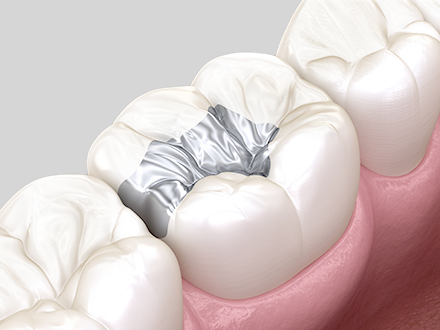

작은 충치나 치아 파절 부위를

자연 치아 색상에 맞춰

빠르게 복원하는 치료입니다.

손상 부위만 소량 제거하여 최대한 치아 보존

자연 치아 색상과 유사해 우수한 심미성

비교적 간단한 치료로 당일에 완료 가능

적은 치료 비용으로 낮은 경제적 부담